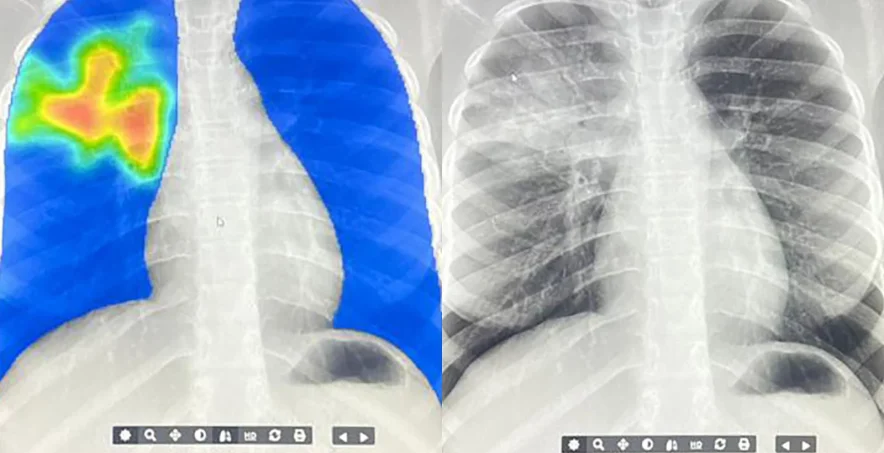

"You can see TB. TB is visual. You have an x-ray. You have a label which says whether they have it or not — and you just train the model," Barzilay says, adding that it only took her a few months and less than $50,000 to make her model. "It's straightforward, very cheap, very fast to develop."